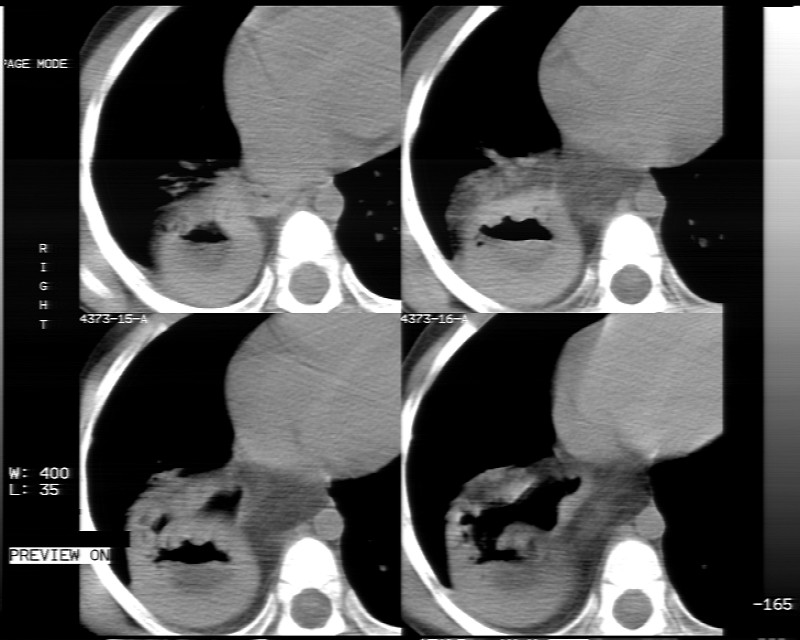

男性,3岁,斜疝术前常规检查胸片体检发现右下肺病变。咳嗽,无发烧。

象腹腔的东西,考虑膈疝

膈疝的表现

内有气体,液平面,考虑食管裂孔疝可能性大。建议食道钡透。

膈疝,可见黏膜·

有液气平面,前部肺纹理聚集(受压改变),周围肺野及相邻胸膜清晰,支持膈疝,可吞服造影剂看一下。

考虑膈疝(右侧胸腹膜裂孔疝?)。